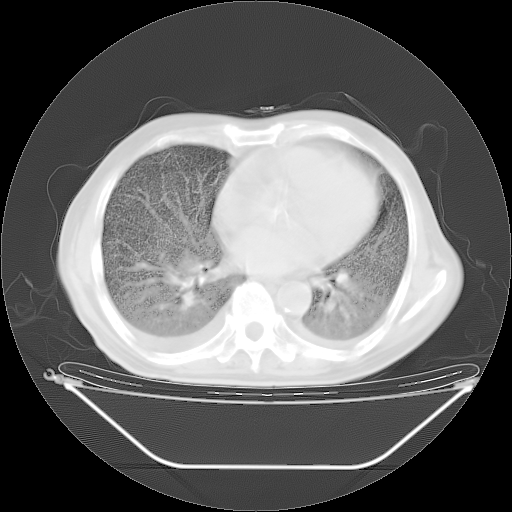

今天复查肺部CT,发现双肺广泛磨玻璃样改变。所以我把3月19日和5月9日相隔50天的肺部CT上传。请大家会诊。

5月9日肺部CT(在4月27日齐鲁医院肺部CT描述部分肺组织磨玻璃样改变,12天后肺组织广泛磨玻璃样改变)

2009年5月9日肺部CT

大致读了系列胸部CT:纵隔窗无明显异常,肺窗:从4、27至今:主要是双肺中下野外带可见毛玻璃样改变,目前处于急性肺泡炎阶段,至于原因考虑1、结替组织或胶原血管性疾病所致?2、恶性疾病如恶组在肺部所致的表现或细支气管肺泡癌?3、药物或其它原因如肺蛋白沉着症所致肺泡炎目前不太可能?总之,明天就去请我院的呼吸科、感染科、血液科和临免专家会诊哈。